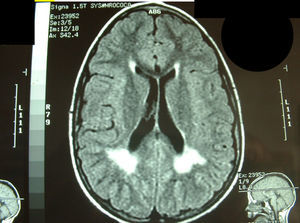

| 18/08/93 | 9/10 | Con 7 años: sospecha ALD-X por TAC y RM (fig. 1) pero AGCML normales | fenómeno miotónico y fenotipo positivos | |||

Fuera del período neonatal, la estrategia diagnóstica pasa por un elevado índice de sospecha6. Debe plantearse ante retraso psicomotor de causa no aclarada, aunque no existan otros signos, como diplejía facial o el fenómeno miotónico clínico en el paciente (no aparece hasta los 3–4 años) o en su madre. En los 2 pacientes (casos 8 y 9) que iniciaron con posturas anómalas de manos se planteó la posibilidad de un cuadro somatomorfo o facticio. El caso 10 presentaba retraso psicomotor y la exploración por neuroimagen, TC y RM (fig. 1), realizadas a los 8 años, mostraba afectación de sustancia blanca periventricular posterior, que había planteado las posibilidades de leucomalacia periventricular y de adrenoleucodistrofia ligada a X. A los 14 años, en un control en consulta, llamó la atención el fenotipo facial y se comprobó la existencia de fenómeno miotónico clínico positivo. Se han descrito las alteraciones de la RM cerebral en la distrofia miotónica tipo 1. En la forma congénita es característica la dilatación ventricular y moderada o grave afectación de la sustancia blanca posterosuperior a los trígonos, alteraciones no correlacionadas con la edad y, por tanto, debidas fundamentalmente a defecto del desarrollo. En las formas del adulto las alteraciones están relacionadas con la duración de la enfermedad y varían de normalidad a ventriculomegalia y alteraciones de sustancia blanca debidas a degeneración7.